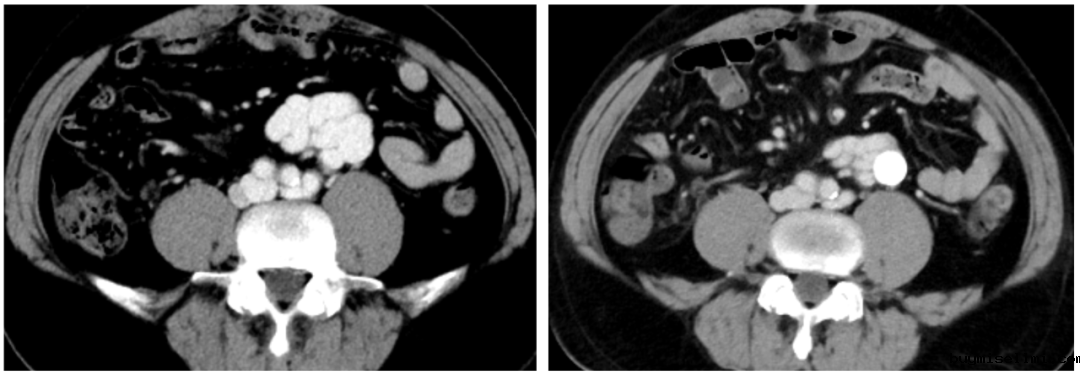

2023-08-10 多排CT全腹部直接增强:肝硬化,脾大,门静脉纤细,食管胃底静脉曲张、异常分流道(肠系膜下静脉-下腔静脉分流,引流端近下腔静脉肾静脉分叉处)

2)腹部增强CT

异常分流道曲张静脉较前显著萎缩